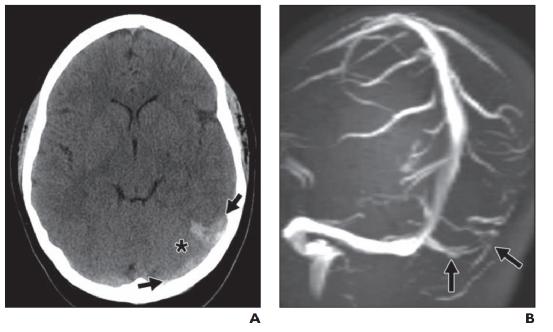

图8-脑静脉血栓形成。A,增强CT图像显示左侧横窦和乙状窦内高密度血栓条索征(箭头)。有细微的邻近血管源性水肿(星号)。B,MR静脉图的旋转最大密度投影图像显示左侧乙状窦充盈缺损(箭头)。T1加权成像异常信号可以证实血栓的存在。

图9-动静脉畸形(AVM)。A,未增强CT图像显示分叶状高密度影伴钙化静脉石(箭头)。注意周围轻度血管源性水肿(星号)。B,CT血管造影显示AVM累及整个左大脑半球,病灶位于左额叶。

在平扫 CT 上,受影响静脉内的高密度凝块可能会产生脐带征。周围的血管源性水肿并不局限于典型的动脉分布(图 8A)。出血性转化很常见,表现为不均匀性和回旋状。CT 静脉造影可以证实存在充盈缺损,上矢状窦血栓形成典型的空三角征。MR 静脉造影也可用于评估脑静脉血栓形成。然而,由于 T2 血流相关伪影很常见,因此应检查 T1 加权序列以验证疑似血栓区域的信号变化(图 8B )。